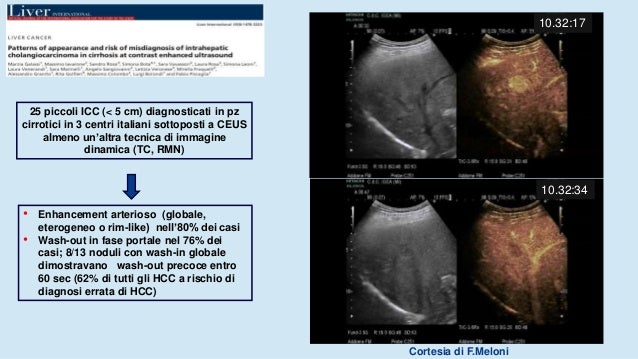

50 Sfumature Di Cirrosi Epatica E Non Solo